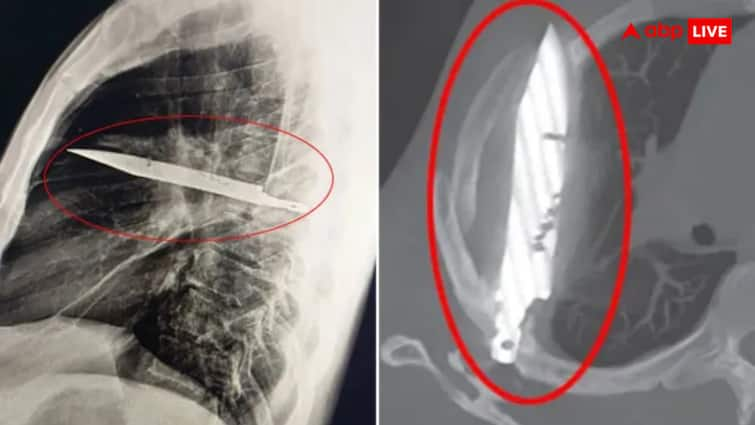

But this time when he was investigated, the real reason came out. The doctors did X-rays and saw that a metal object was stuck in his chest. Actually, it was a knife blade that entered the chest near his right shoulder during the quarrel eight years ago. The biggest surprise was that the blade remained there for so many years without harming a big limb. Neither touched the heart, nor the lungs nor any pulse. Because of this, the person never felt pain or discomfort and no one understood the need for a re -examination.

The problem increased when pus and dead tissue gradually started accumulating around that blade. For this reason, pus started coming out of the nipple. When the doctors knew the truth, they immediately decided to undergo surgery. During the operation, that blade was taken out with great care. Also, the dead tissue and deposited pus nearby was also cleaned. After this, the patient was kept in the ICU for 24 hours and then monitored in the normal ward for 10 days. The good thing is that the patient is now completely healthy and no problem was revealed in follow-up.